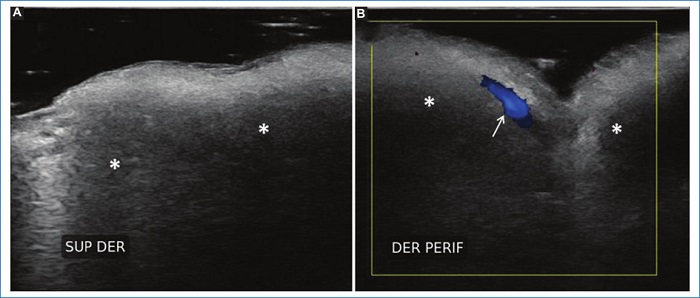

Del grupo 1 (n = 53, 63% del total de pacientes), 51 (96,2%) pacientes eran de sexo femenino y 2 (3,7%) de sexo masculino, 24 (45,2%) no presentaban rellenos previos, 15 (28,3%) presentaban ácido hialurónico (AH) y 14 (26,4%) tenían rellenos permanentes (biopolímeros, silicona y polimetilmetacrilato). Además, 12 (22,6%) pacientes de este grupo presentaron variantes anatómicas, de los cuales solo uno tenía un relleno previo de AH. Entre las variantes encontradas se mencionan arterias angulares, labiales, nasal dorsal y temporal profunda en sitios habituales de inyección de rellenos, glándulas parótidas prominentes y venas intercantales prominentes en sitios de inyección frecuentemente utilizados (Figs. 1, 2 y 3). En este grupo se presentaron 2 (3,7%) pacientes con prótesis faciales. Del total de pacientes que integraron este grupo, el informe ecográfico modificó la conducta del médico estético en el 60% (32) de ellos.

Asimismo, se observaron dos pacientes con una glándula parótida de tamaño muy prominente como variante constitucional (sin signos inflamatorios), que condicionaron un cambio del plano de inyección de rellenos para evitar un depósito intraglandular inadvertido. El depósito de rellenos intraglandulares inadvertidos podría desencadenar posteriormente una inflamación glandular2,15.

Además, la preexistencia de AH, material de relleno biodegradable, ampliamente utilizado en la actualidad, debería ser tomado como precaución ya que, si se coloca nuevo material, se podría condicionar una sobre corrección, con la consecuente deformación del rostro, o bien un edema regional (puesto que el AH atrae el agua). Cada caso debería ser valorado individualmente2,16. Además, regiones sensibles como la región nasal, que carece de tejido fácilmente distensible, podría sufrir eventos vasculares por compresión vascular extrínseca debido a la sola ocupación de espacio (especialmente la punta de la nariz).

En un paciente sin rellenos ni elementos protésicos en su rostro se necesitan aproximadamente 100.000 bacterias por gramo de tejido para desencadenar una infección. Este valor baja a 100 bacterias por gramo de tejido en caso de implantes17. En relación con esto, algunos médicos inyectores prefieren no realizar tratamientos mínimamente invasivos en la región que presente una prótesis subyacente ya que, si se desarrollara un proceso infeccioso en el implante, este debería ser retirado. En nuestra muestra tuvimos dos pacientes con elementos protésicos, uno en la región del mentón y otro malar, ninguno de los dos fue inyectado en dichos sitios. Con la ecografía se pudo delimitar el sitio exacto de la prótesis y dirigir el tratamiento estético a otras regiones faciales.